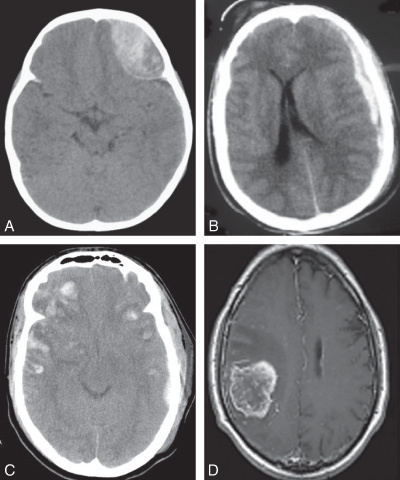

Quel diagnostic pour chaque photo?

a =hématome extradural

b=hématome sous dural

c=contusions cérébrales

d= tumeur cérébrale